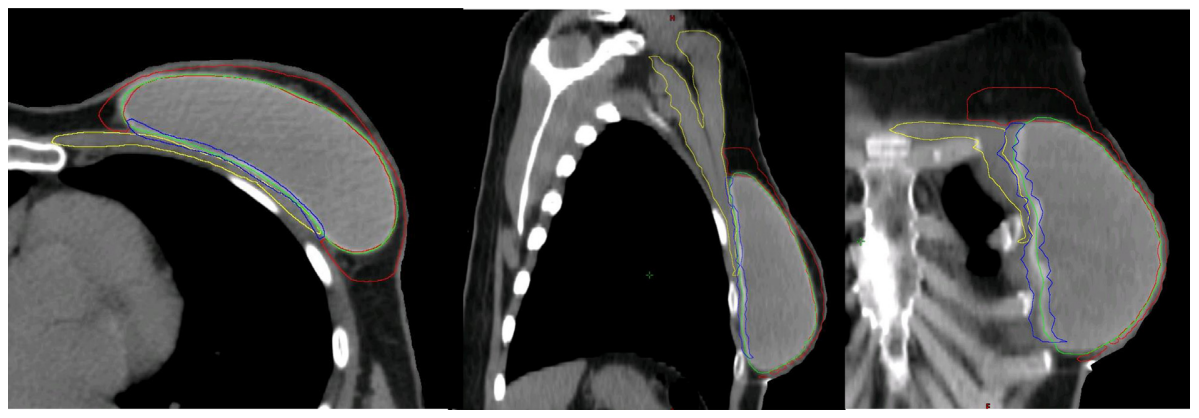

Hình 4c. CTVp_chestwall với phần trước (Đỏ) và sau (Xanh biển) trong trường hợp túi độn trước cơ ngực (Xanh lá cây). Cơ ngực (Vàng)

Sau IBR-i sử dụng túi độn trước cơ ngực, CTVp_chestwall bao gồm 2 phần phân chia bởi túi độn:

(1) Phần trước: Giữa da và túi độn, chứa đựng mạng lưới bạch huyết dưới da và mô tuyến tồn dư (Nếu có) (Hình 4C, thể tích giới hạn bởi đường viền đỏ);

(2) Phần sau: Giữa túi độn và cơ ngực/thành ngực, chứa đựng mô tuyến tồn dư (Nếu có) (Hình 4c, thể tích giới hạn bởi đường viền xanh biển); chỉ trở thành một phần của CTV trong các trường hợp có các yếu tố khối u bất lợi (Bảng 1).